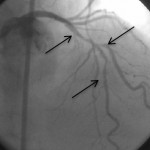

Çatallanma yapan üç damara 3 tel yerleştirilerek üç damara aynı anda müdahale ediliyor.